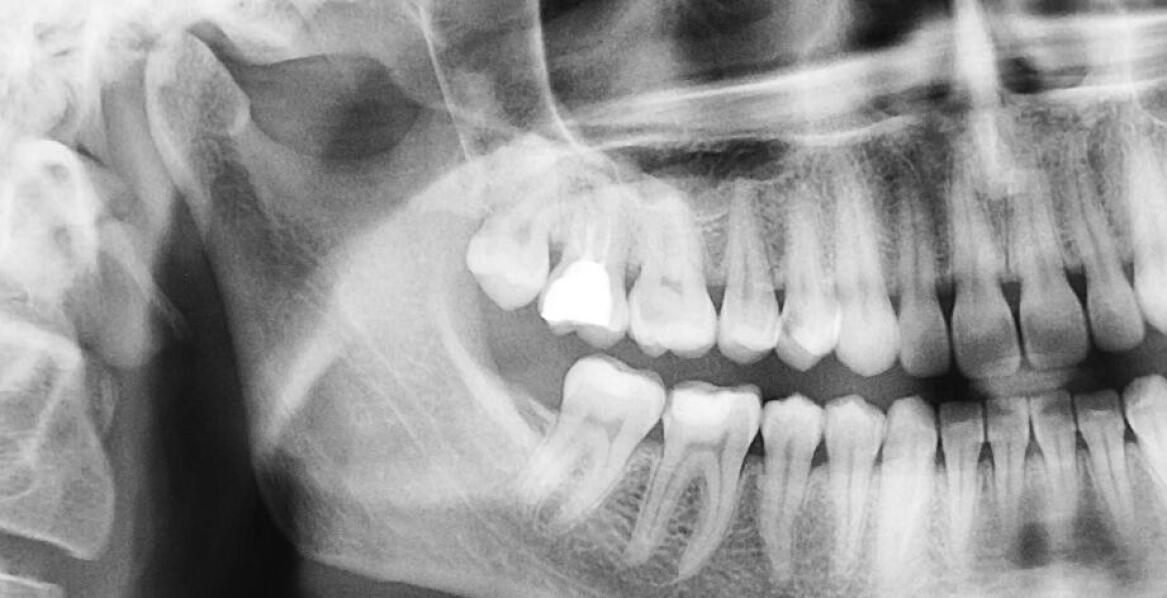

Precyzyjne pomiary rentgenowskie odgrywają kluczową rolę w planowaniu zabiegów stomatologicznych, zwłaszcza w kontekście endodoncji. Nowoczesne technologie pozwalają uzyskać obrazy o wysokiej jakości, co przekłada się na dokładną diagnozę oraz skuteczne leczenie. Warto zwrócić uwagę na znaczenie tyc